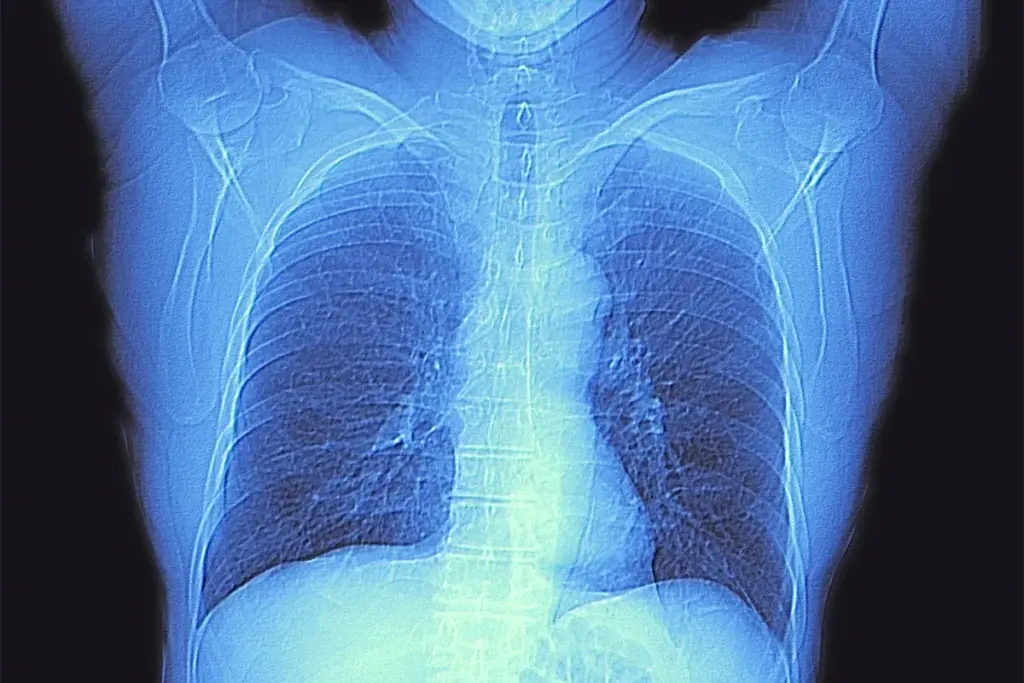

A precise cancer diagnosis is essential for creating an effective treatment plan. The process begins with a physical exam and a review of medical history. While imaging tests like CT scans, MRIs, and PET scans provide images of a tumor’s size and location, a biopsy is the definitive diagnostic tool. This involves removing a small tissue sample for a pathologist to examine. Blood tests may also be used to detect tumor markers. This collective data is then used to “stage” the cancer, a critical step that determines the extent of the disease.

• Imaging Tests: CT, MRI, and PET scans produce detailed images of organs and tissues to detect tumors and measure their size.